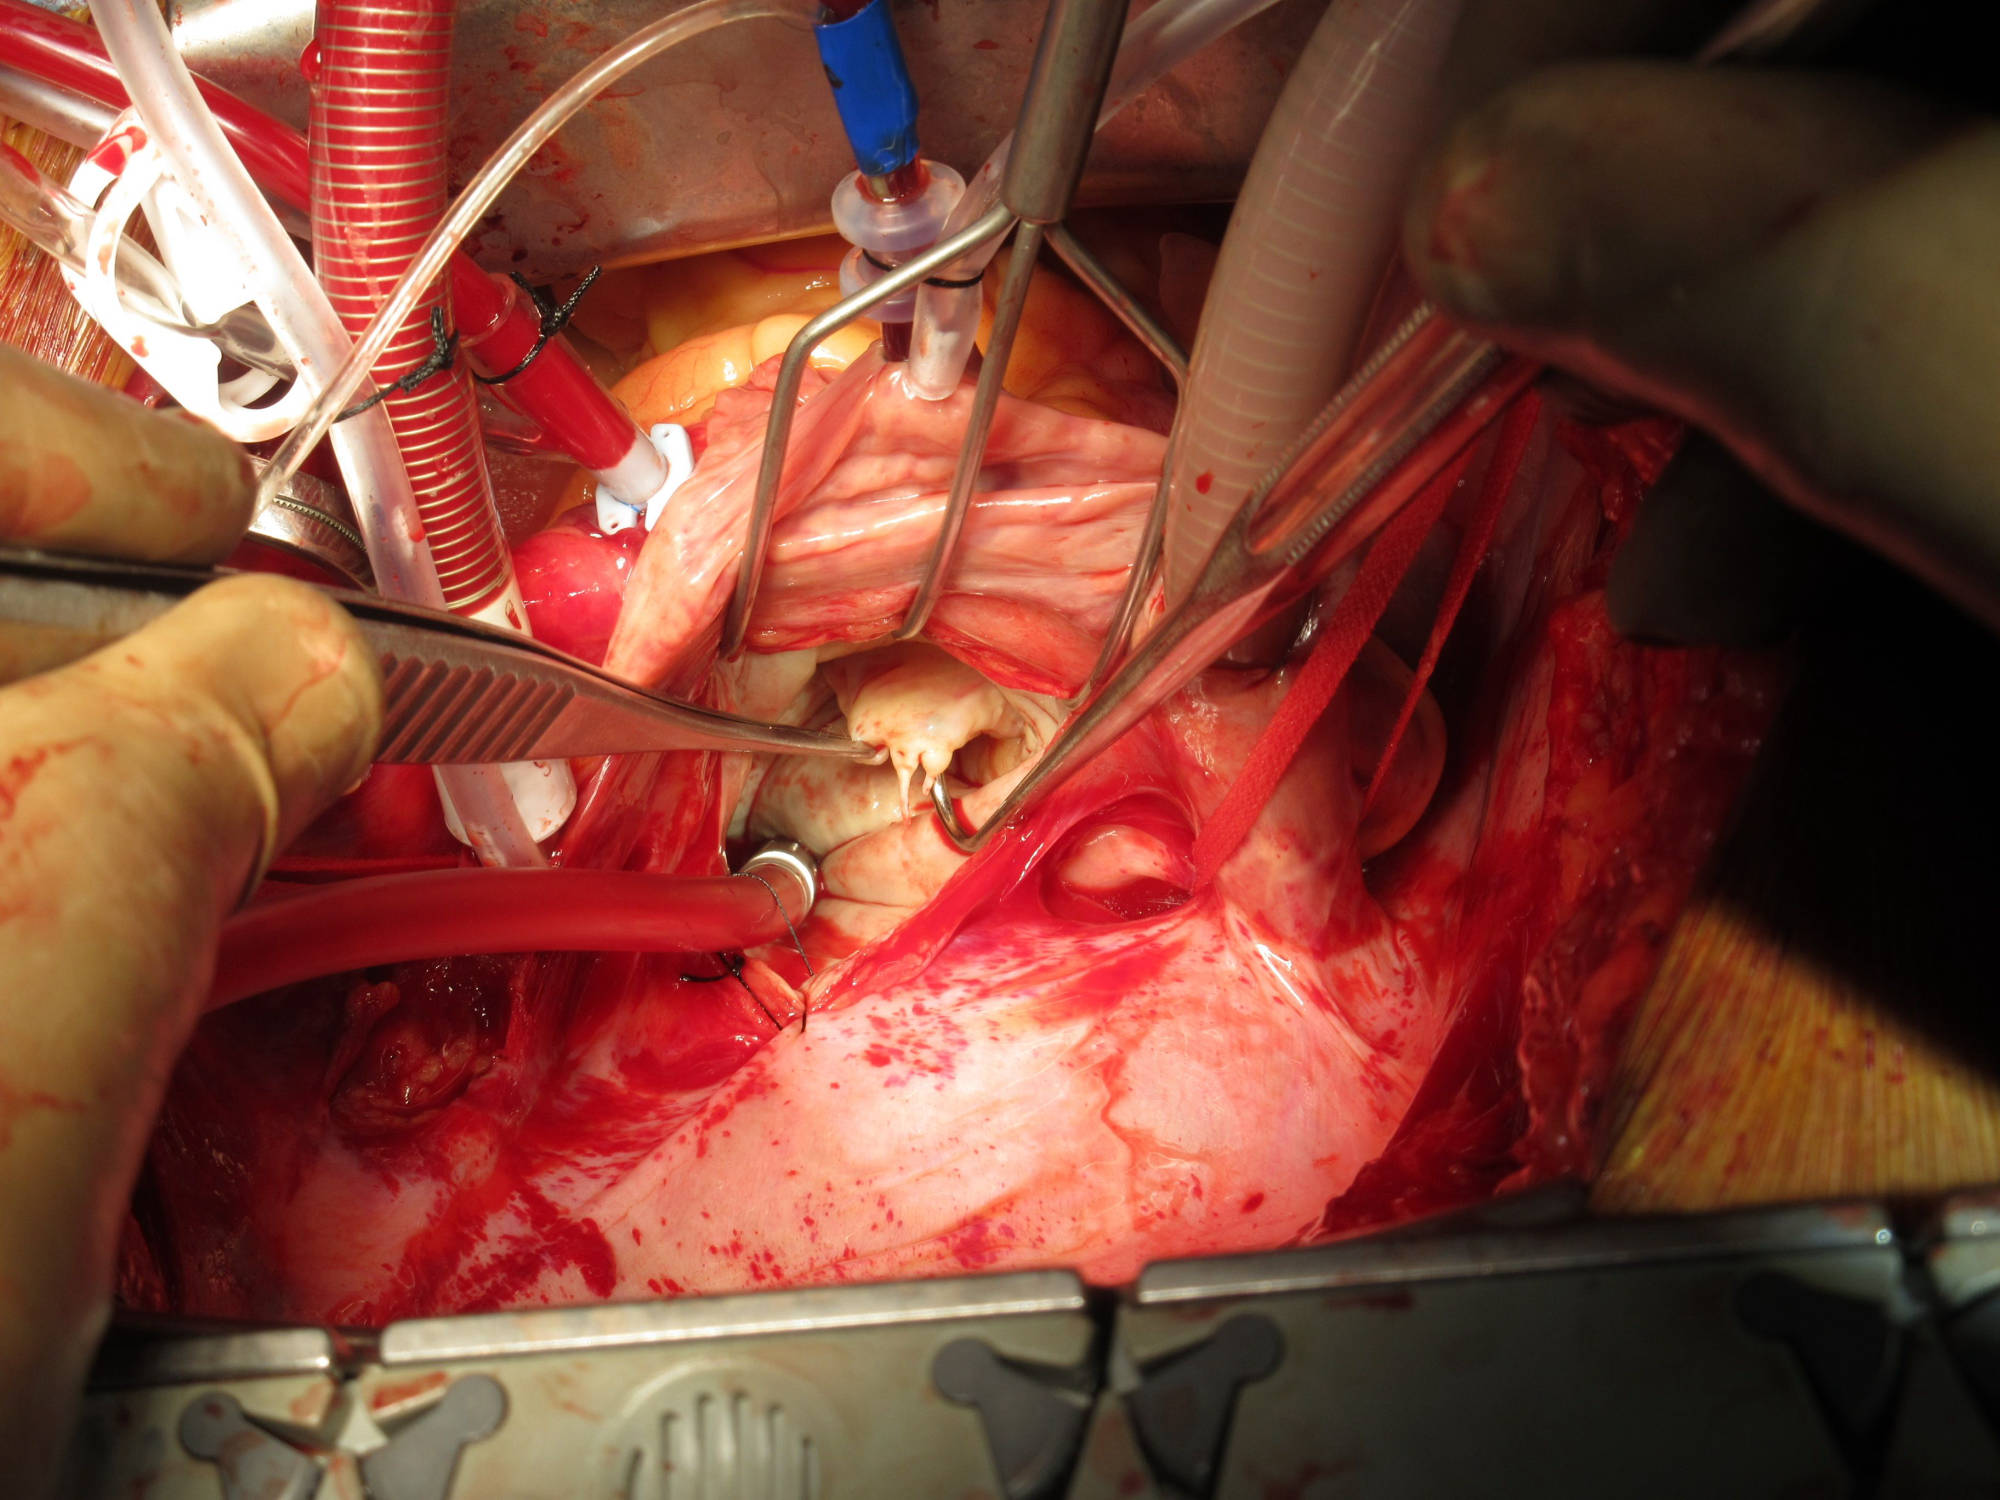

Mitral Valve Repair

Wherever possible, repair of the mitral valve is performed. This is superior to replacement since it retains the native valve. We have excellent long term results (over 20 years) with no significant leak.